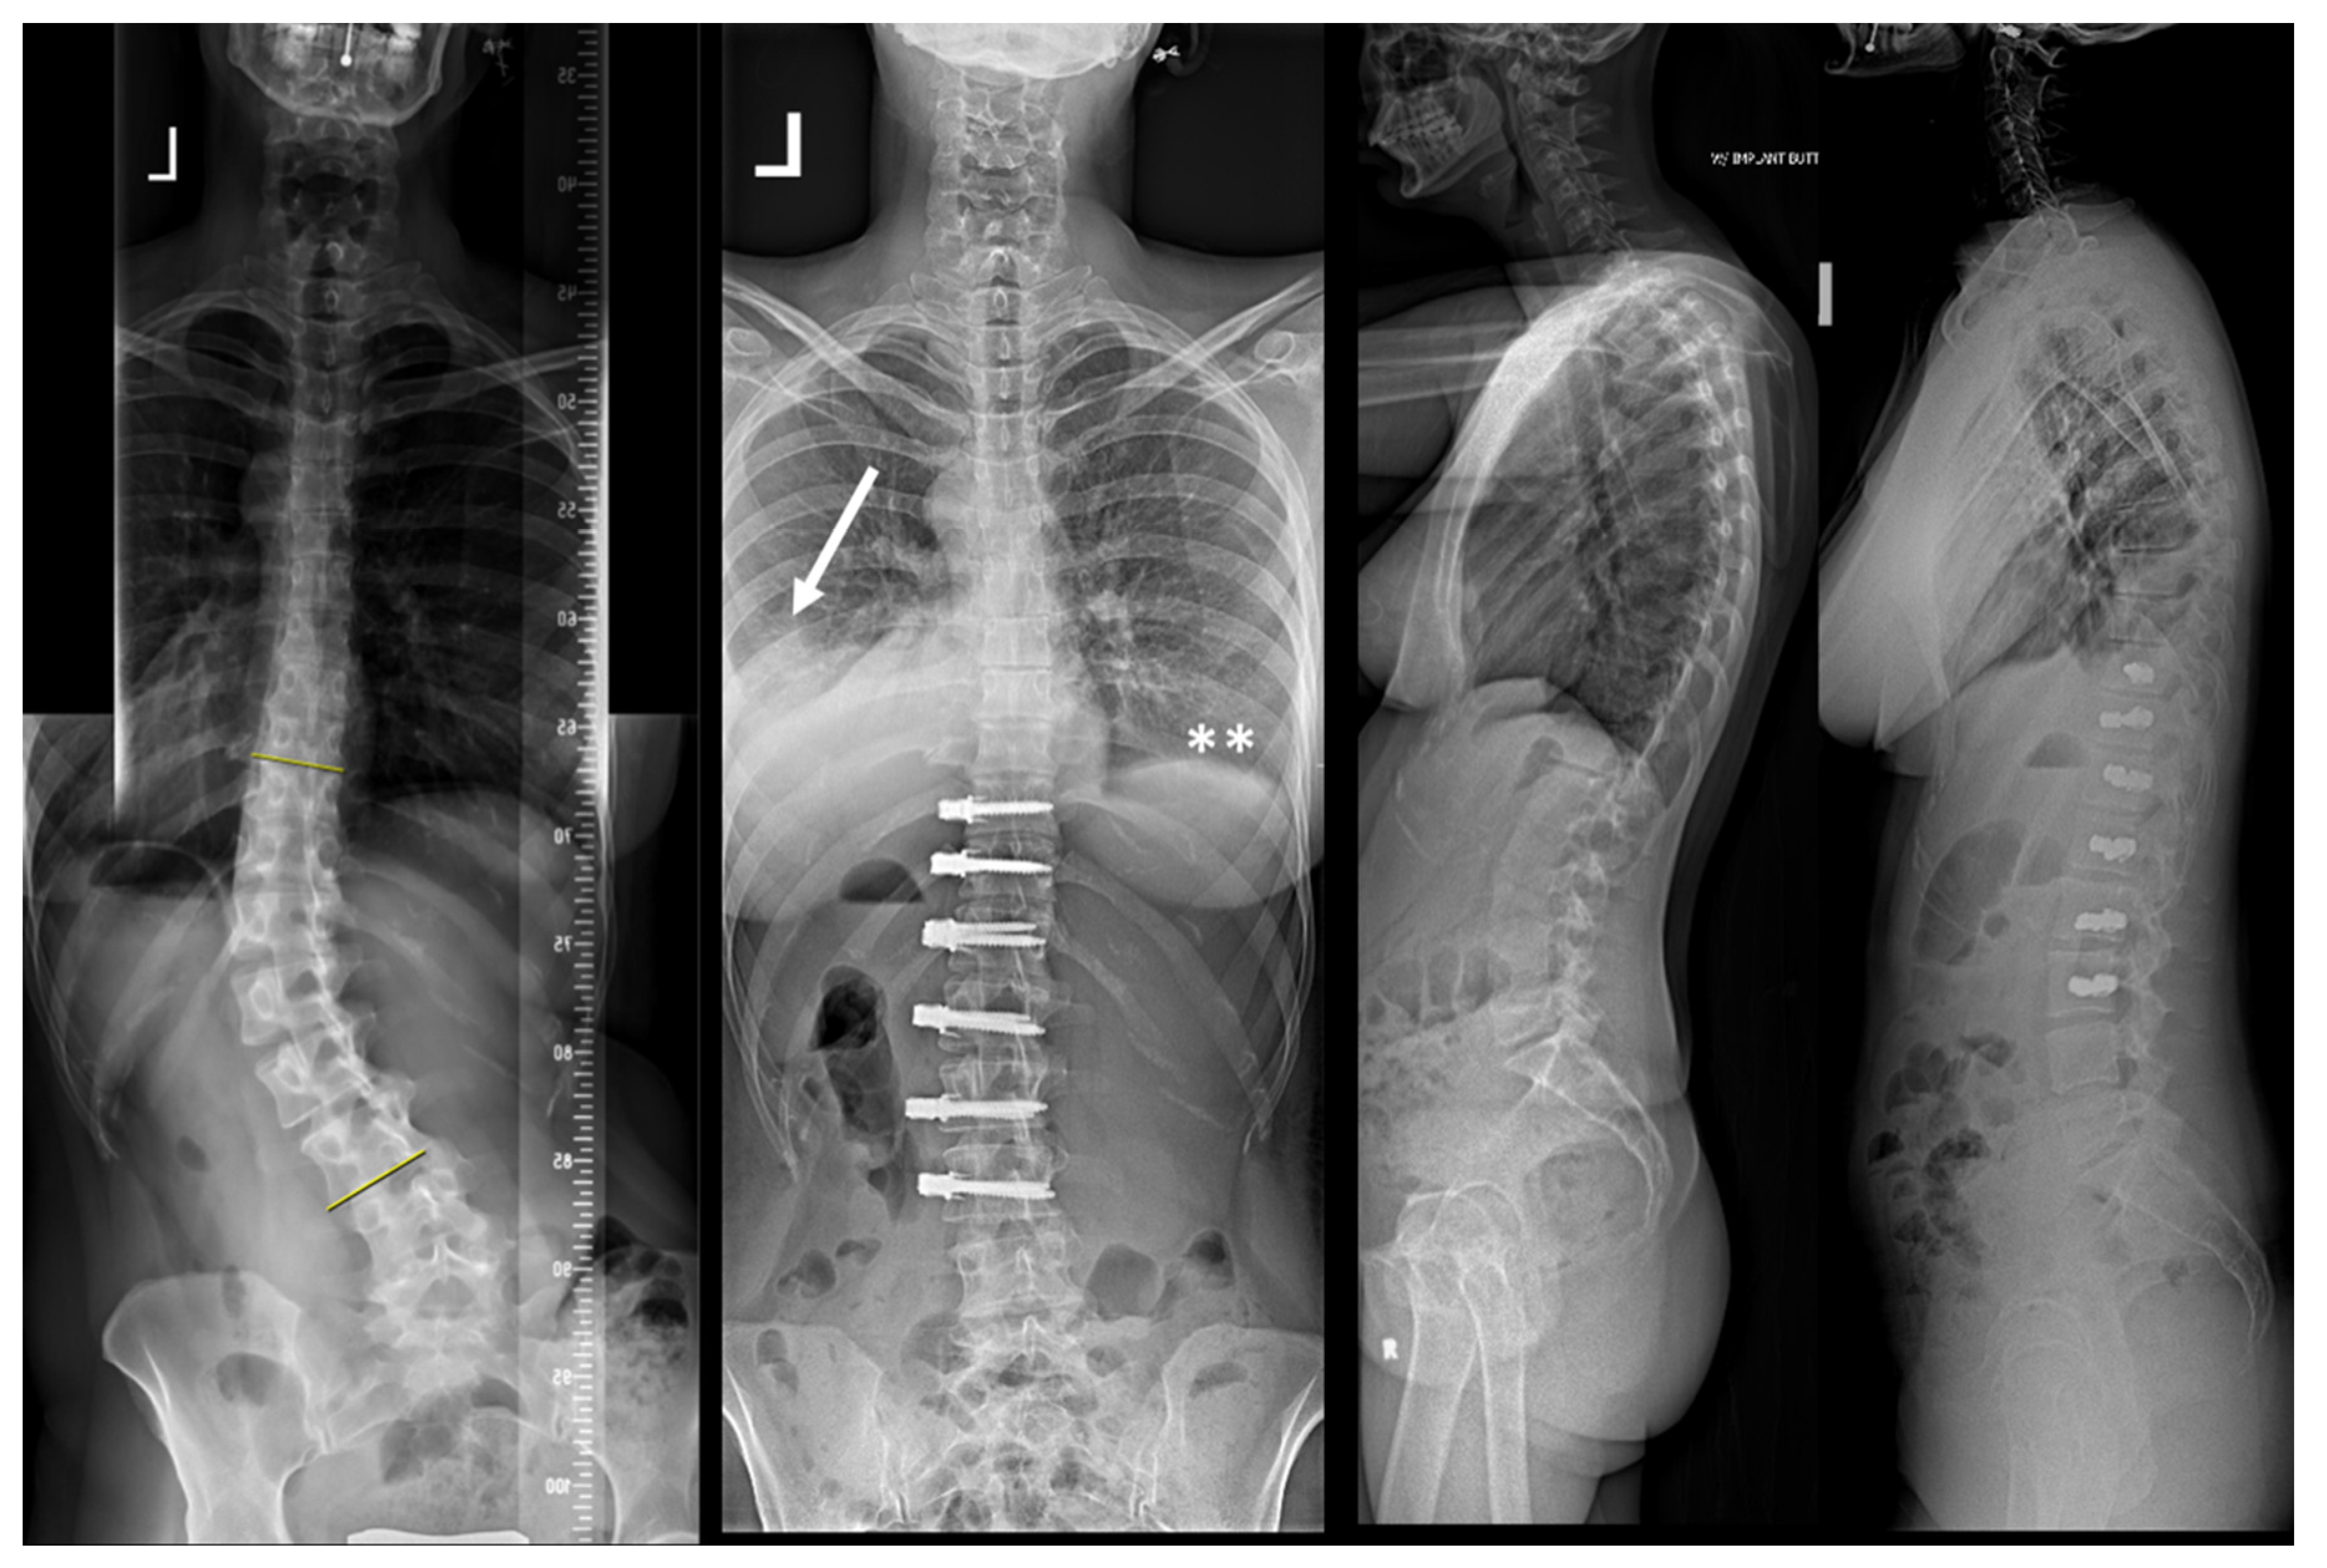

| 1 | 13.3 | F | 2 | T5-T12 right T12-L4 left | Pleural effusion | 2 weeks | Right | Minor dyspnea | Ultrasound, conservative treatment |

| 2 | 17.6 | F | 4 | T6-L1 right | Pleural effusion | 2 weeks | Right | Dyspnea, fatigue | 2 × aspiration |

| 3 | 16.2 | F | 4 | T5-T12 right | Contralateral atelectasis | 2 days | Left | Severe dyspnea | Re-intubation for 3 days, 3 bronchoscopies and removal of a mucus plug |

| 4 | 17.6 | M | 1 | T9-L3 right | Pleural effusion | 4 weeks | Right | Chest pressure | Chest tube reinsertion |

| 5 | 16.2 | F | 2 | T5-T11 right T11-L3 left | Pleural effusion | 3 weeks | Bilateral | Chest pain and elevated CRP levels | Bilateral aspiration, forced diuresis and i.v. albumin treatment |

| 6 | 17.7 | F | 2 | T5-T11 right T11-L3 left | Chylothorax | 3 days | Right | None effusion, diagnosed on routine post-op X-ray | Chest tube reinsertion and dietary restriction |

| 7 | 16.8 | M | 2 | T5-T11 right T11-L4 left | Pleural effusion | 3 weeks | Left | Unknown | Explorative thoracoscopy |

| 8 | 17.9 | F | 1 | T10-L3 left | Pleural effusion | 4 days | Left | None, effusion diagnosed on routine post-op X-ray | Aspiration followed by chest tube reinsertion for recurrent effusion |

| 9 | 14.6 | F | 2 | T5-T11 right T11-L4 left | Pleural effusion | 3 weeks | Right | Fatigue, dyspnea | Chest tube reinsertion, antibiotics for co-existing pyelonephritis |

| 10 | 14.3 | F | 1 | T11-L4 left | Pleural effusion with concomitant infection | 3 weeks | Left | Sudden sharp pain in the left chest and dyspnea | Attempted aspiration and chest tube without output. VATS and six weeks antibiotitcs because of postivie culture for staph epidermidis |

| 11 | 12 | F | 4 | T5-T11 right | Haematothorax | 1 day | Right | No symptoms, significant blood loss noticed after declamping the chest tube and drop of haemoglobin levels | Emergency explorative thoracotomy using the same surgical approach. No active bleeding found but clotted hematoma |

| 12 | 13 | F | 2 | T6-T12 right T12-L4 left | Haematothorax | 6 weeks | Right | Acute chest pain | Emergency explorative thoracotomy |

| 13 | 16.5 | M | 1 | T10-L4 left | Pleural empyema | 5 weeks | Left | Dyspnea, elevated CRP levels | VATS and antibiotic therapy |

| 14 | 16.3 | F | 2 | T5-T11 right T11-L4 left | Pleural effusion | 5 weeks | Right | Dyspnea | Aspiration |